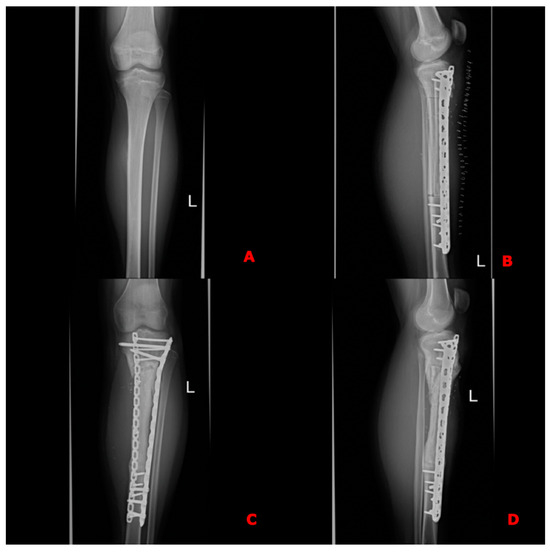

Since the tumors were located within the shafts of the long bones, with no involvement of the epiphyses in any case, reconstructions were performed using long diaphyseal intercalary grafts. The allograft combined with the fibula free flap was secured to the proximal and distal stumps of the tibia using locking compression plates (Figure 4D,E and Figure 5). These plates were used to facilitate earlier weight-bearing ambulation.

Figure 5. X-rays of the case shown in the figure above. (A) Preoperative X-ray of histopathologically confirmed osteosarcoma of the left tibia; (B) X-ray taken on the 1st postoperative day after resection of a specimen and receonstruction of the defect using the Cappana method, confirming the proper axis of the reconstructed bone, bony anastomoses and correct positioning of the free flap. (C,D) Follow-up X-rays in the 15th postoperative month with visible bone union and restored proper axis of the lower limb.